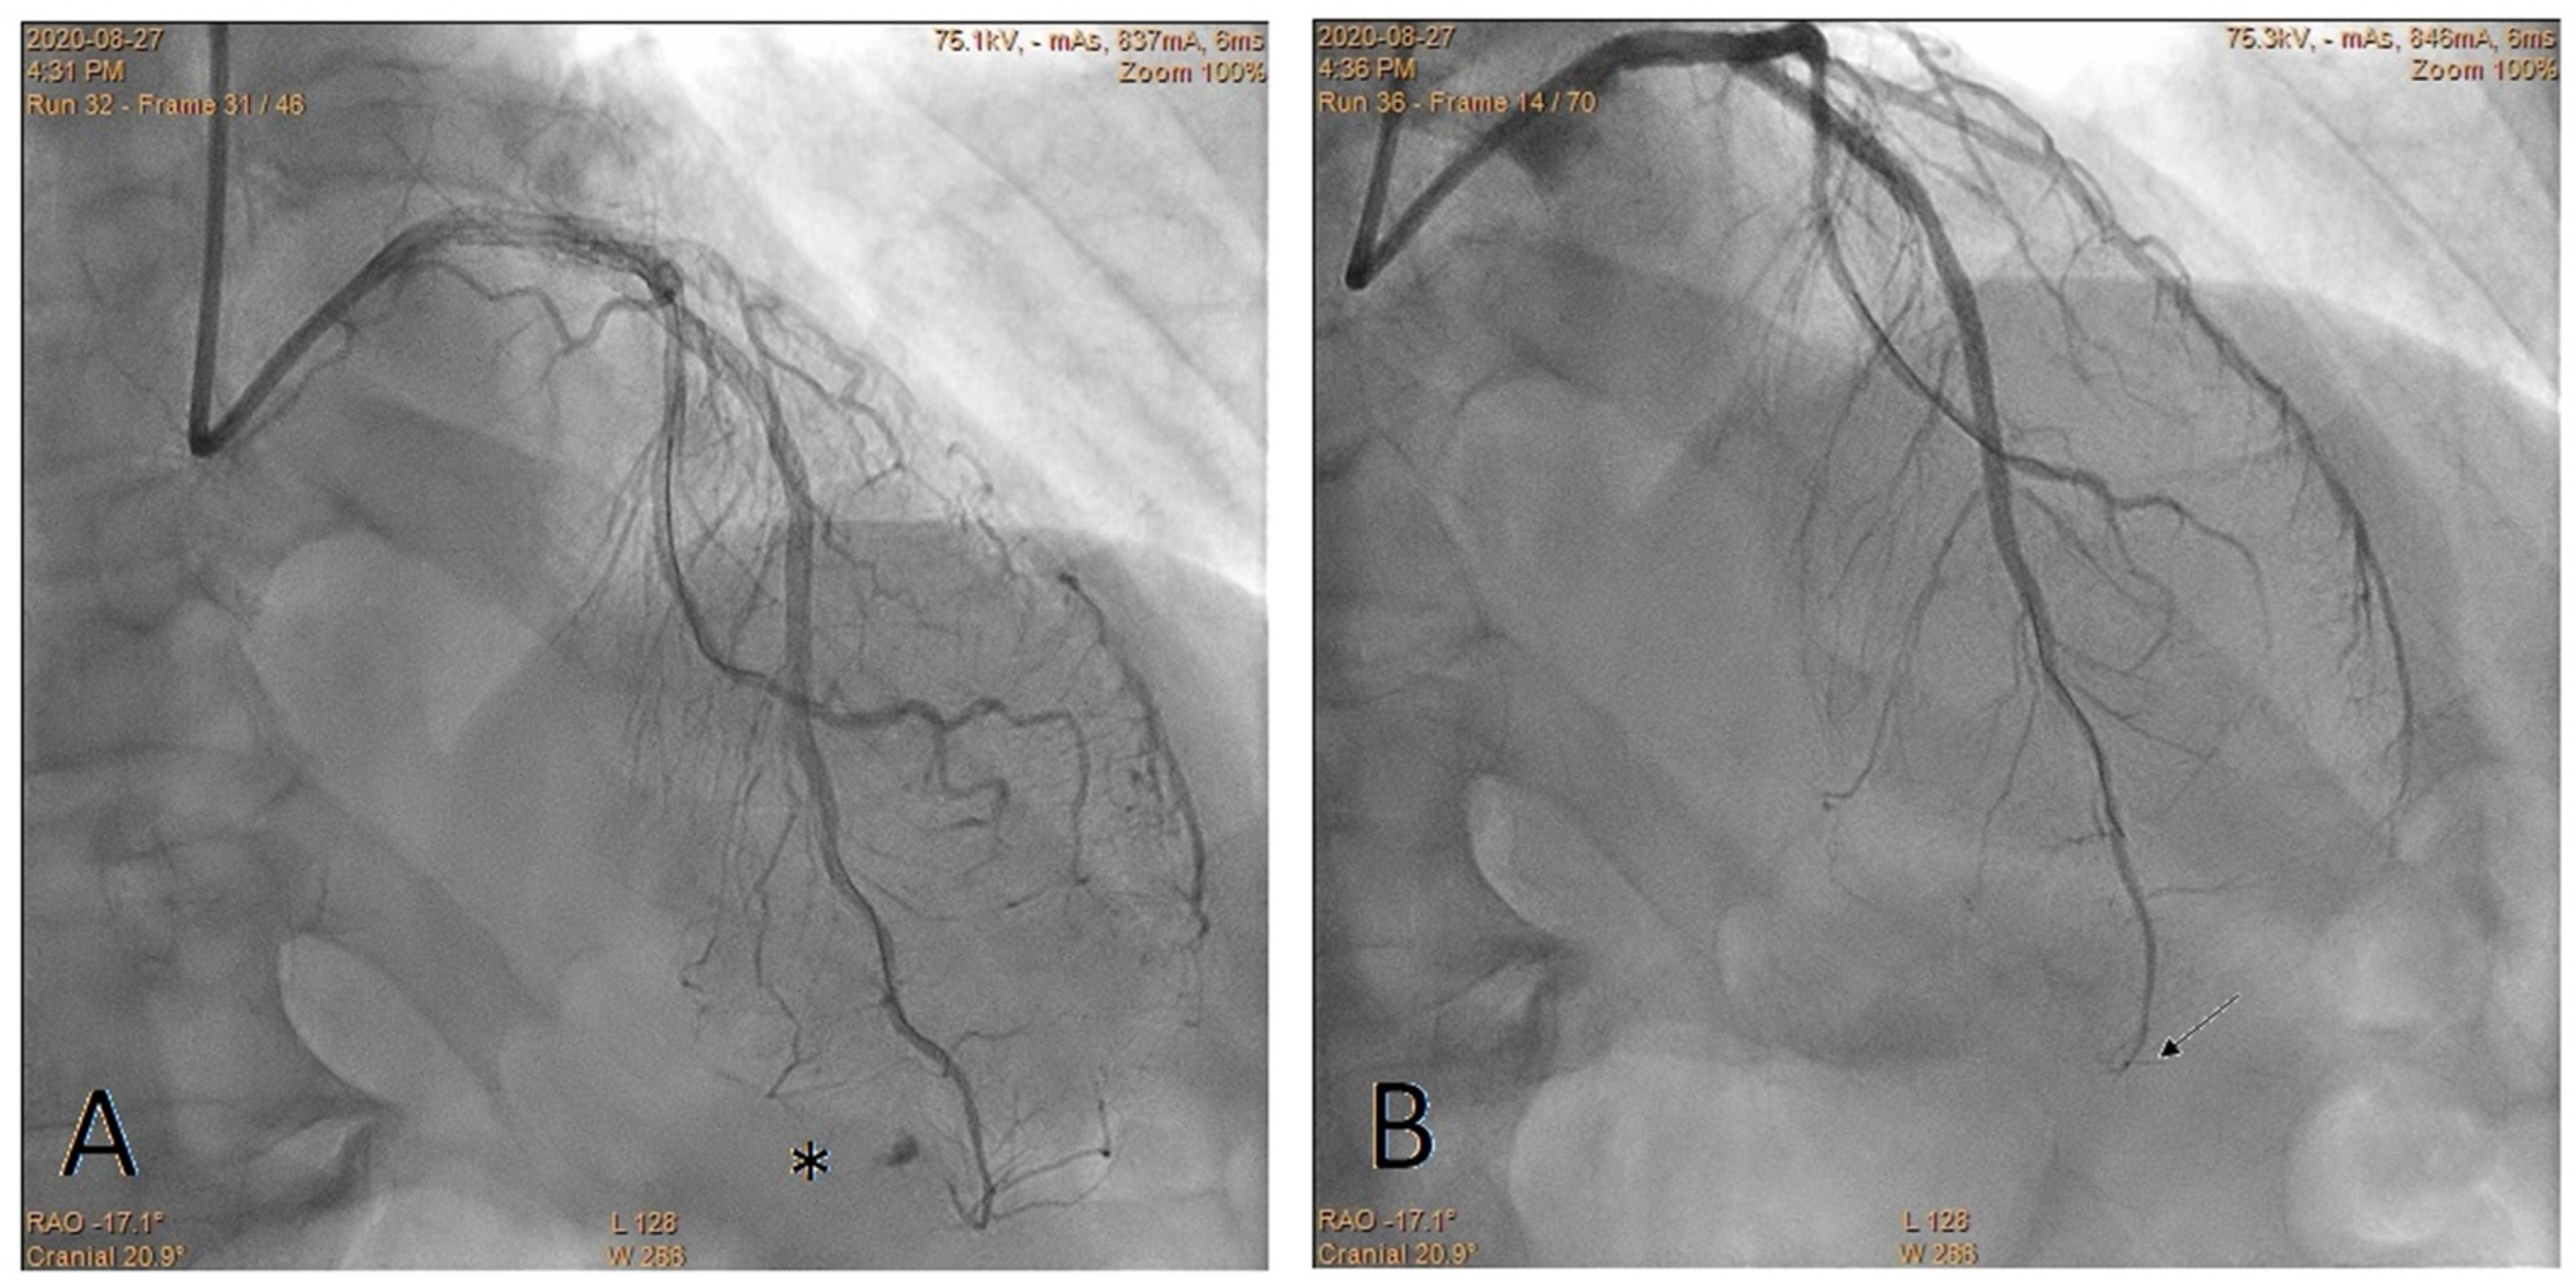

Embolization of Perforated Coronary Artery with a Fragment of Balloon Catheter (Cut Balloon Technique)—Multicenter Study

2. Methods

3. Results